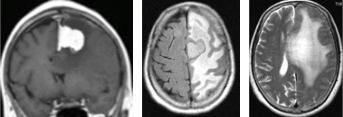

この患者さんには当初手術を勧めましたが(左)、拒否されたため画像検査のみの経過観察としましたが、1年後の画像所見では嚢胞成分(液体が貯留している部分)は縮小し(右)、充実成分の大きさは変わっていませんでした。初診から6年経過していますが、何事もなく経過しご本人も満足されています。

その他にも様々な場所に髄膜腫ができます。大きさが小さい病変は偶然に発見されます。

これらはすべて手術をせずに経過観察しています。(勿論放射線照射もしていません)